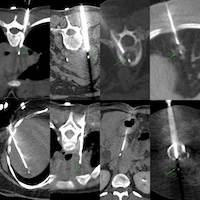

Current Case:

59-years old with fever and non-resolving consolidation

What would be your approach?

The video below describes the case and the reason for performing a biopsy parallel to the vessels and not perpendicular